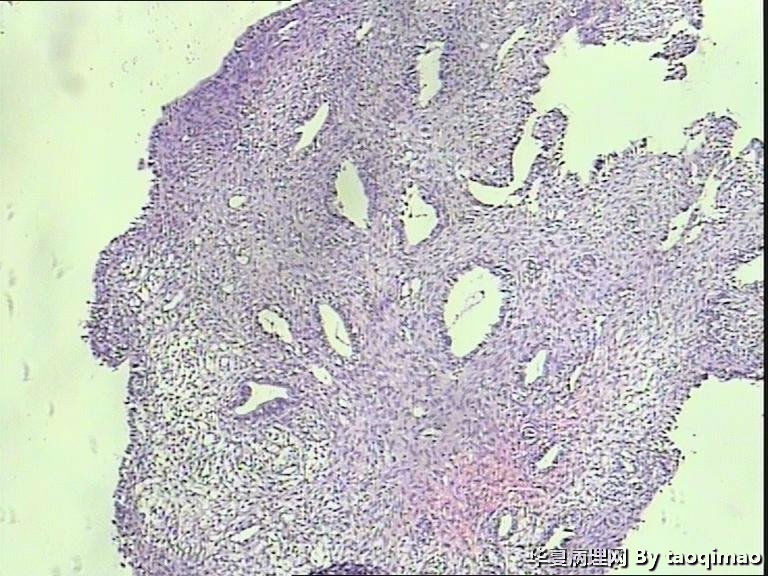

功血,滋养细胞浅肌层?

图1

这是患者第一次刮宫的内膜,怎么出报告呢